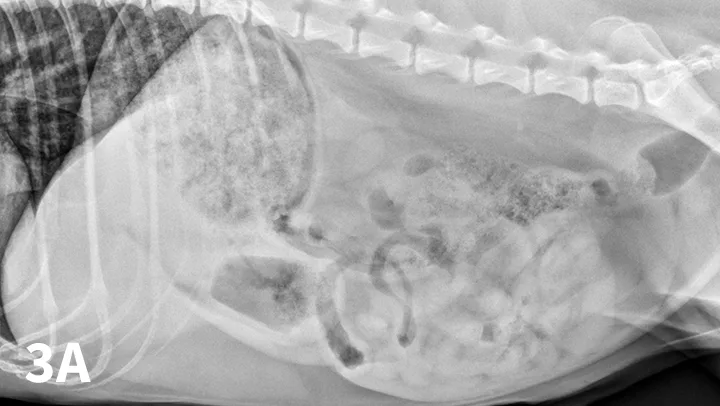

Figure 7A depicts a left lateral abdominal radiograph of a dog with dilated loops of bowel. Figure 7B depicts a left lateral abdominal radiograph of a dog with a wooden spoon being used to compress the abdomen.

Left lateral radiograph of a 9-year-old Jack Russell terrier with a 4-day history of vomiting and anorexia (A). Moderate dilation with small gas bubbles (stars) of the small intestinal tract is noted (B). Left lateral compression radiograph of the same dog. A wooden spoon was used to apply compression to the caudal abdomen. Ventral to the colon, a well-defined ovoid mineral opacity (arrows) is visible within a dilated small intestinal loop. This was a piece of rubber confirmed at surgery.

With the patient in lateral recumbency and using a wooden or plastic spoon or paddle, the abdomen is mildly compressed in an area of concern identified on survey films (Figure 7A). Using the paddle and compression, adjacent bowel or masses are displaced to increase radiographic conspicuity. This results in better visualization of potential foreign material (Figure 7B), plication of small intestinal loops in cases of linear FBs, or intestinal masses otherwise obscured by superimposed bowel.